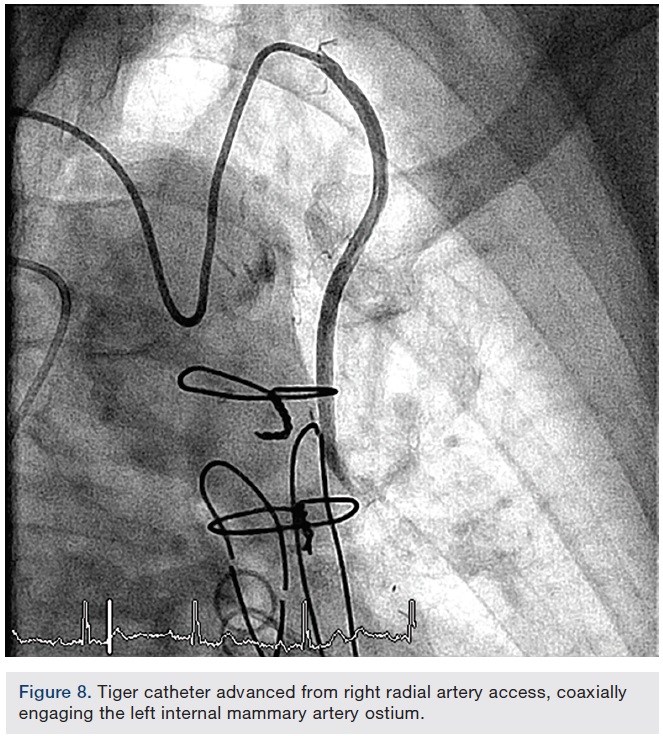

Медицинские исследования: Ангиография и катетеризация